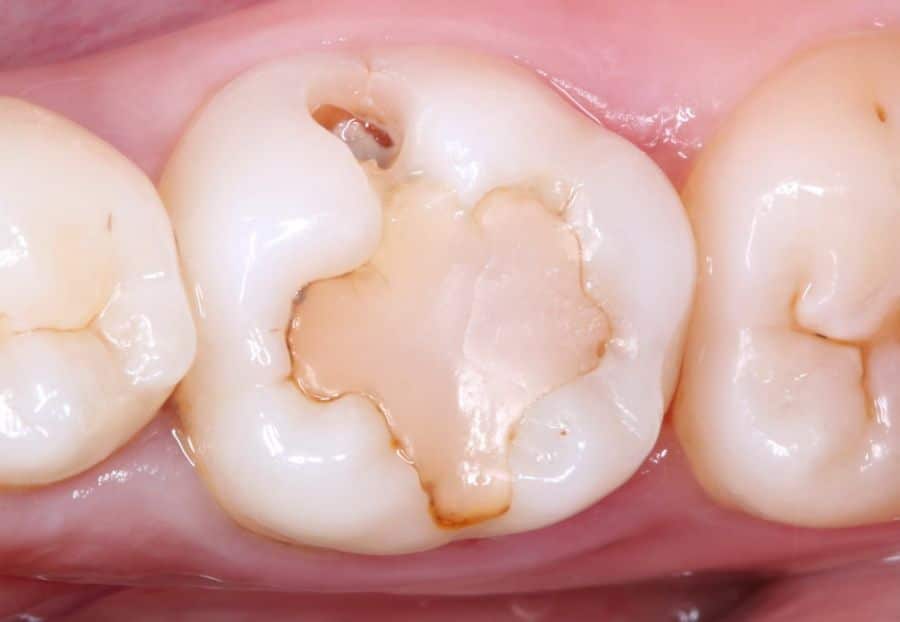

Carisolv and Brix 3000 are a very conservative (minimal tissue removal) caries treatment system. It combines a liquid and some special instruments. While it has no effect on healthy dental tissue, it dissolves the decaying dental tissue of caries.

The Carisolv® system dissolves dental tissue with caries in a very controlled and conservative manner, without damaging surrounding healthy tissue